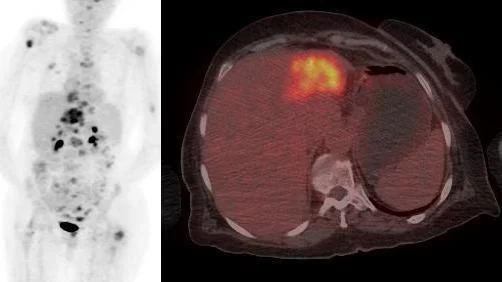

A 70-year old woman was diagnosed with a 3 cm inhomogeneous liver lesion, but did not attend a planned biopsy. An ultrasound examination after a year showed no growth of the lesion, and her case was terminated. Eight years later she presented with general discomfort, a 25 kg weight loss, fever, muscular pain, a raised erythrocyte sedimentation rate, and an elevated plasma concentration of C-reactive protein. A computed tomography (CT) of the chest and abdomen revealed multiple bone metastases throughout the skeleton, an atrophic left liver lobe, dilated hepatic ducts, and some enlarged retroperitoneal lymph nodes. A cholangiocarcinoma was suspected. A subsequent F-18-FDG PET/CT scan of the head, chest, and abdomen (Fig. 1) showed avid FDG uptake in the bone metastases, the known 3 cm lesion in a now atrophic left liver lobe, the right adrenal gland, the enlarged retroperitoneal lymph nodes, and near the head of the pancreas, supporting the diagnosis of cholangiocarcinoma.

Figure 1: FDG uptake in the bone metastases